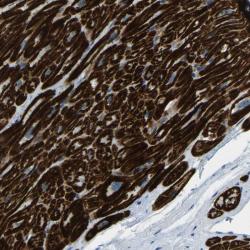

- Experimental details

- Immunohistochemical staining of human heart muscle shows strong cytoplasmic positivity in myocytes.

- Validation comment

- Two independent antibodies targeting one protein yielding similar staining patterns. Staining pattern consistent with experimental and/or bioinformatic data.